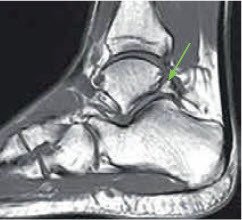

Bei der klinischen Untersuchung fällt insbesondere die ausgeprägte Druckempfindlichkeit oberhalb der Ferse medial und lateral der Achillessehne auf. Die Schmerzen können durch eine forcierte Beugung im Sprunggelenk verstärkt werden. Bei der bildgebenden Untersuchung, unter anderem anhand eines Kernspintomogramms, ist ein Os trigonum erkennbar.

Beim Os trigonum handelt es sich um einen angeborenen sogenannten akzessorischen (zusätzlichen) Knochen, der bei etwa 7 Prozent der Bevölkerung auftritt. Im Verlauf der körperlichen Entwicklung kommt es in bestimmten Skelettregionen zur Verschmelzung von Knochenkernen. Bei ausbleibender Verschmelzung können derartige akzessorische Knochen entstehen, so auch das Os trigonum, welches eigentlich zwischen dem 8. und 11. Lebensjahr mit dem Sprungbein verschmelzen sollte. Es befi ndet sich hinter dem Sprunggelenk und vor der Achillessehne. Dabei muss das Os trigonum nicht unbedingt Beschwerden verursachen. Es sind vor allem sportlich aktive Patienten, wie zum Beispiel Fussballspieler oder Balletttänzer, die im Lauf ihrer Karriere mit Beschwerden konfrontiert werden. Auch ein Umknicken des Fusses kann Schmerzen hervorrufen, die nur langsam oder eben gar nicht mehr vollständig abklingen.